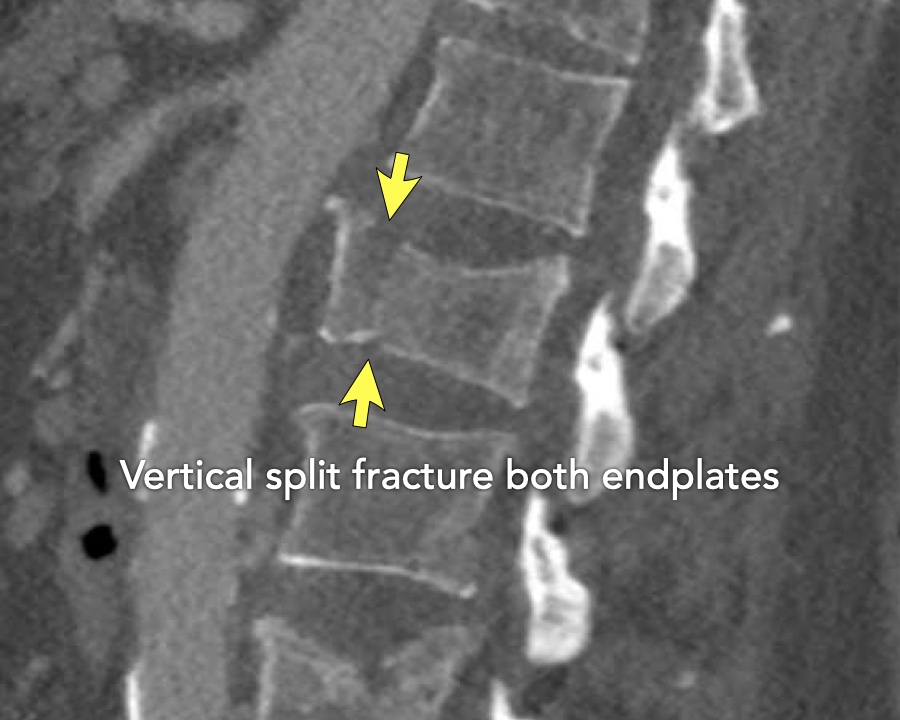

A2 Split fracture

A2 is a fracture of both endplates without involvement of the posterior wall of the vertebral body.

What is the highest AO-type of injury?

Findings:

- No C or B injury

- Fracture of the vertebral body with involvement of both endplates (1+1 points), no posterior wall involvement

Conclusion

injury type A2